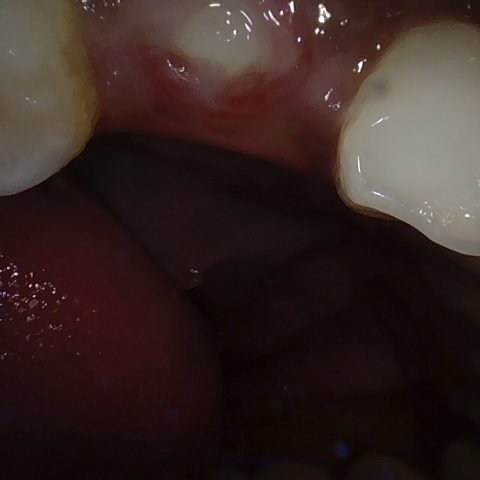

Annotated as "Good"